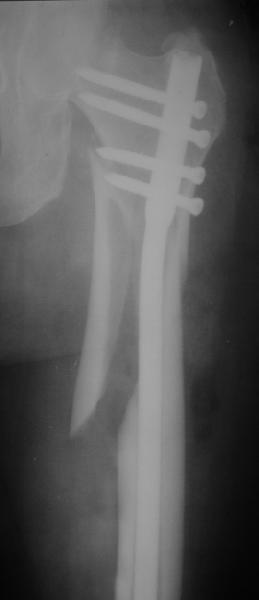

> При межвертельных переломах с цефаломедуллярными гвоздями бывает,

> что проксимальый винт проходит или черед периферический отломок, или

> прямо над ним. И если остался диастаз, то этот винт при осевой

> нагрузке не дает сблизиться отломкам. Пример остеосинтеза в застарелом

> случае в приложении. В качестве предупреждающей меры можно долотом

> разрушить латеральную стенку дистального отломка под винтом.

Конечно, мы не синтезируем остеопорозые вертельные переломы согласно прилагаемому примеру, винты 6 мм вырежутся. Но у более молодых при хорошем качестве кости такие или подобные гвозди с поперечным расположением винтов вполне применимы для меж- и подвертельных переломов.